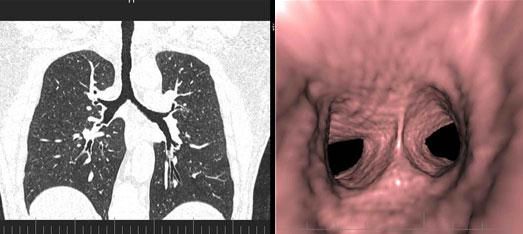

三、先進的仿真内鏡技術:

從多角度,多平面分析空腔髒器病變,可應用于胃、結腸、血管、氣管支氣管、膽道等仿真内鏡檢查,大大提高了病變的檢出率和診斷的準确性。

四、全尿路成像及骨關節三維成像。

全尿路成像(CTU):